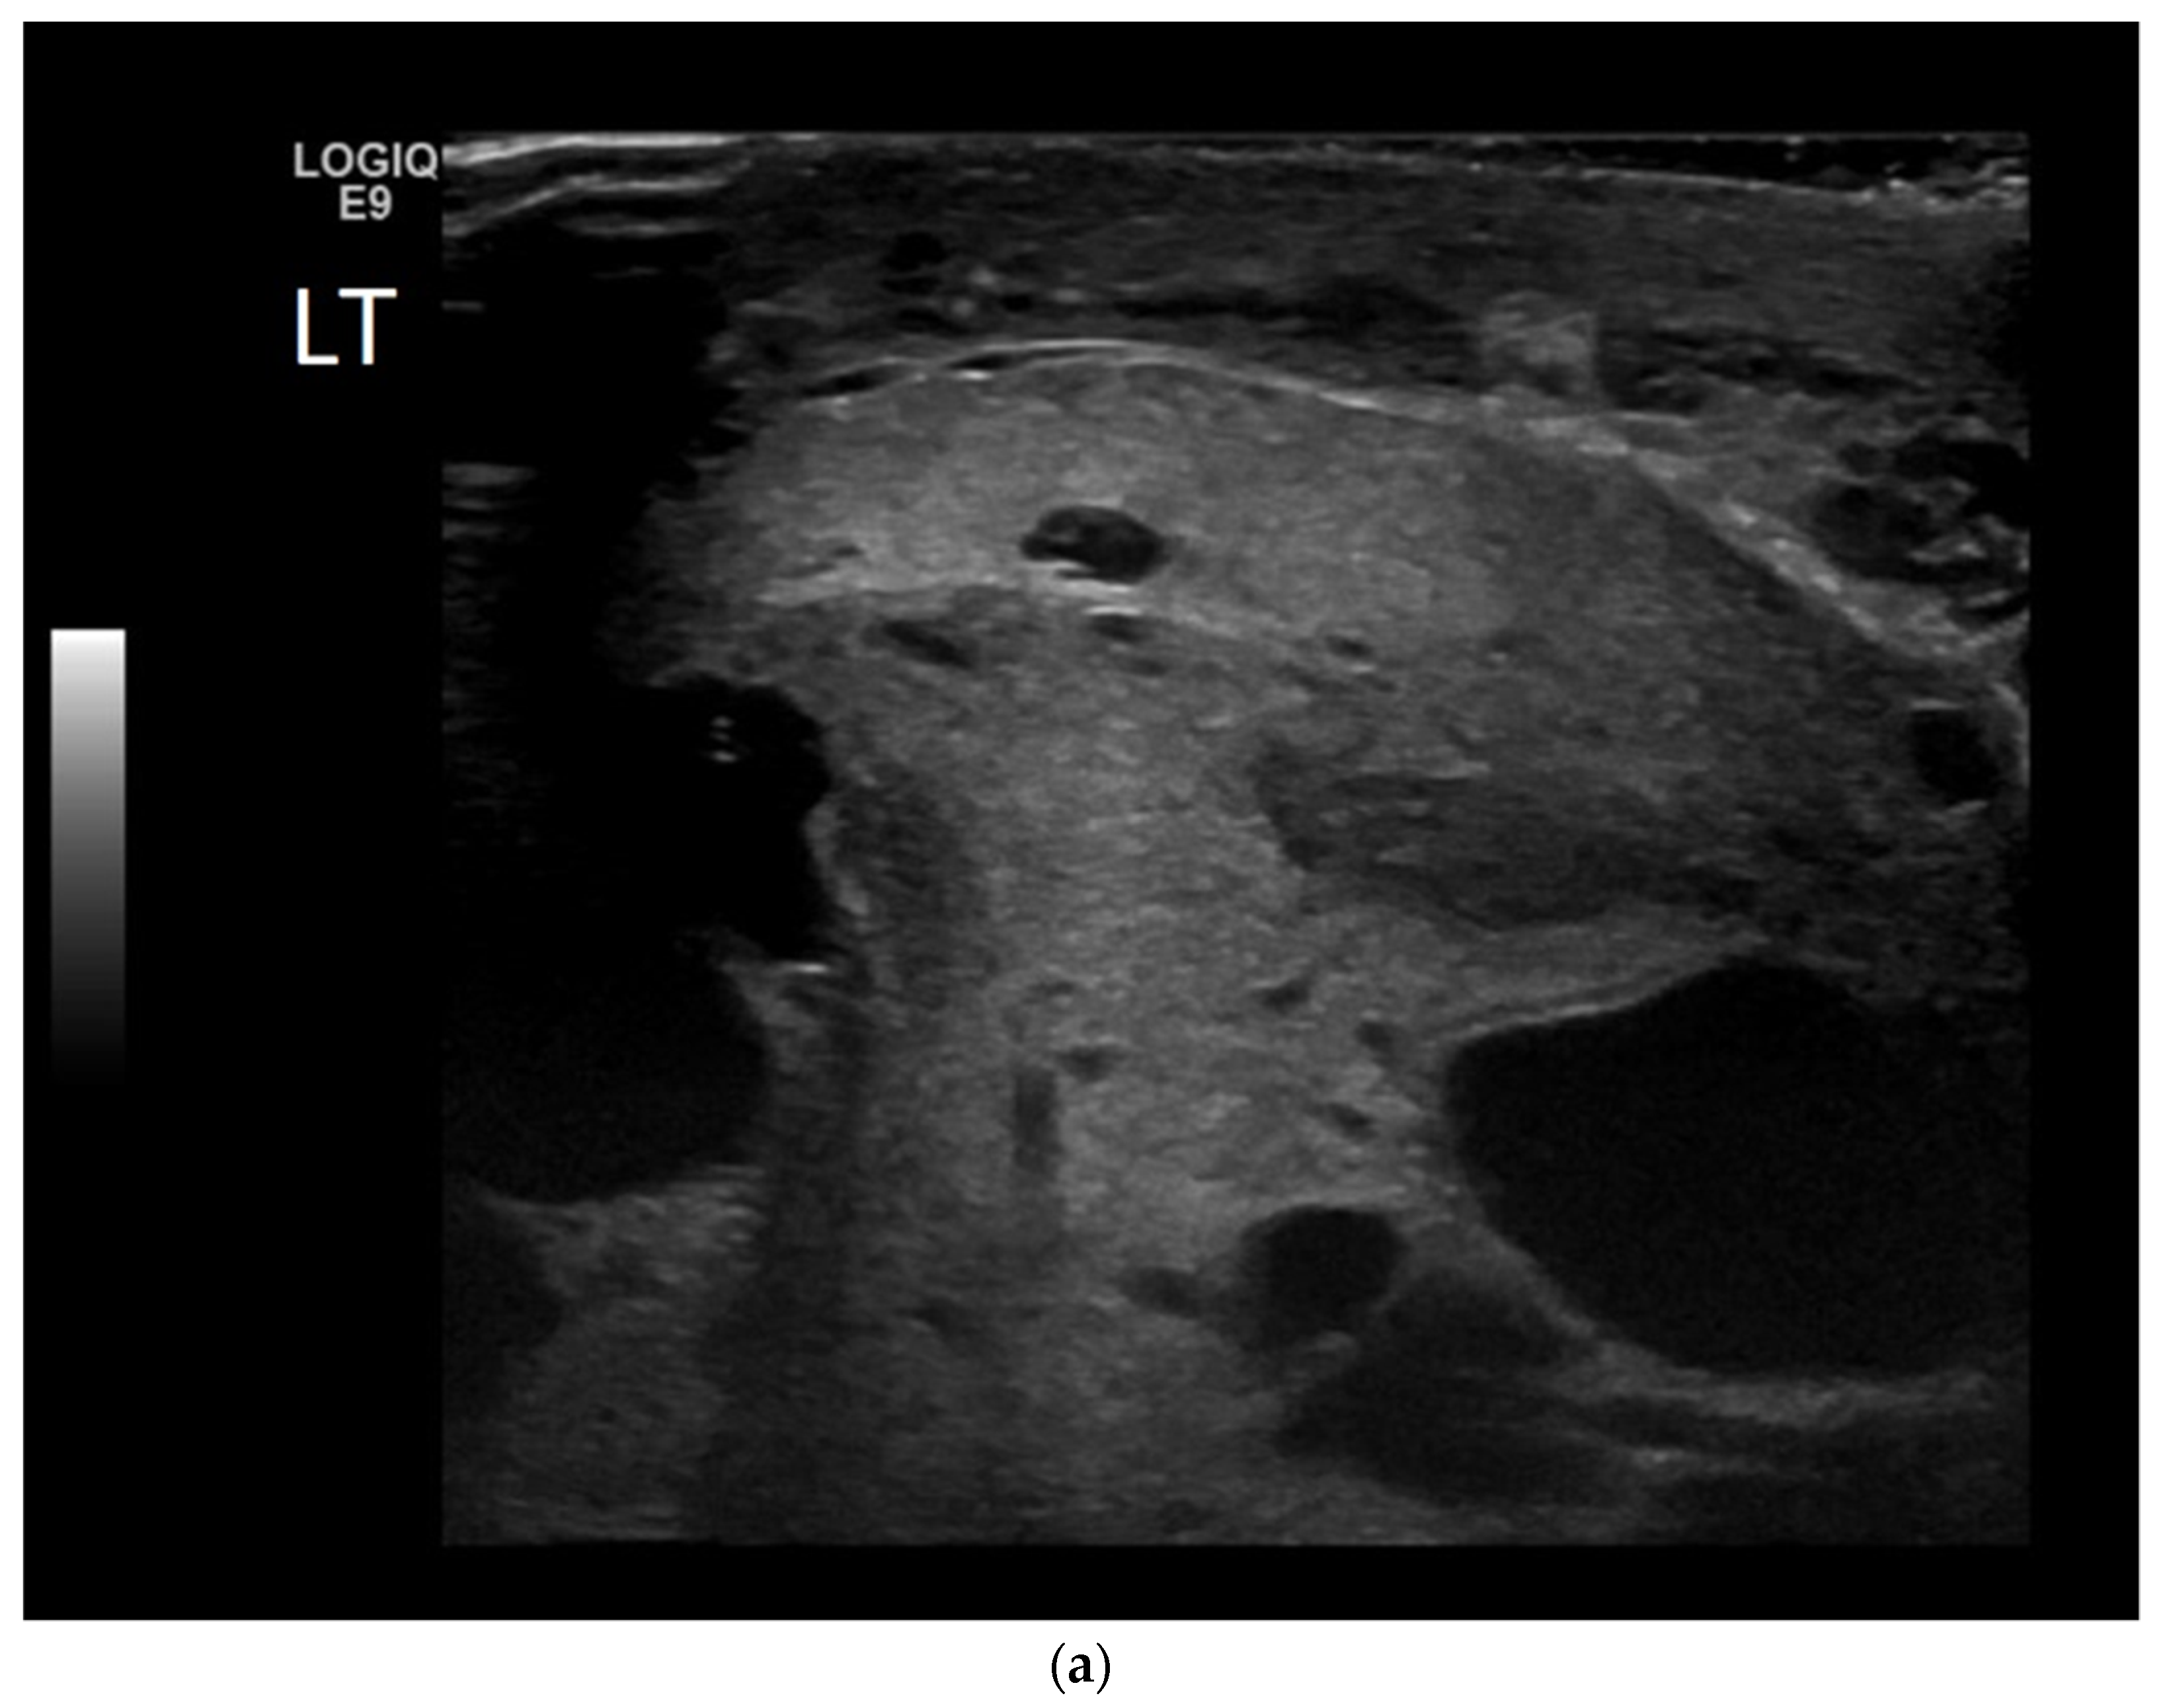

4.1. Seminomatous Germ Cell Tumour

| Seminomas | Homogenous and hypoechoic Well circumscribed Occasionally contain cystic components or calcifications |